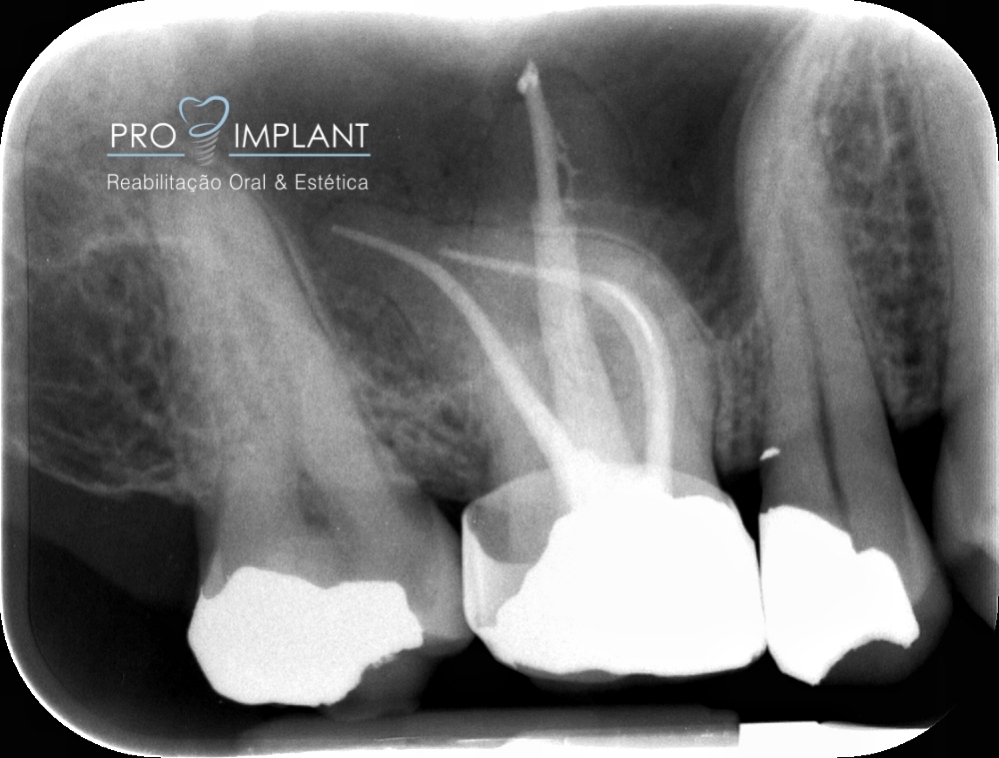

FOTOS

Endodontia